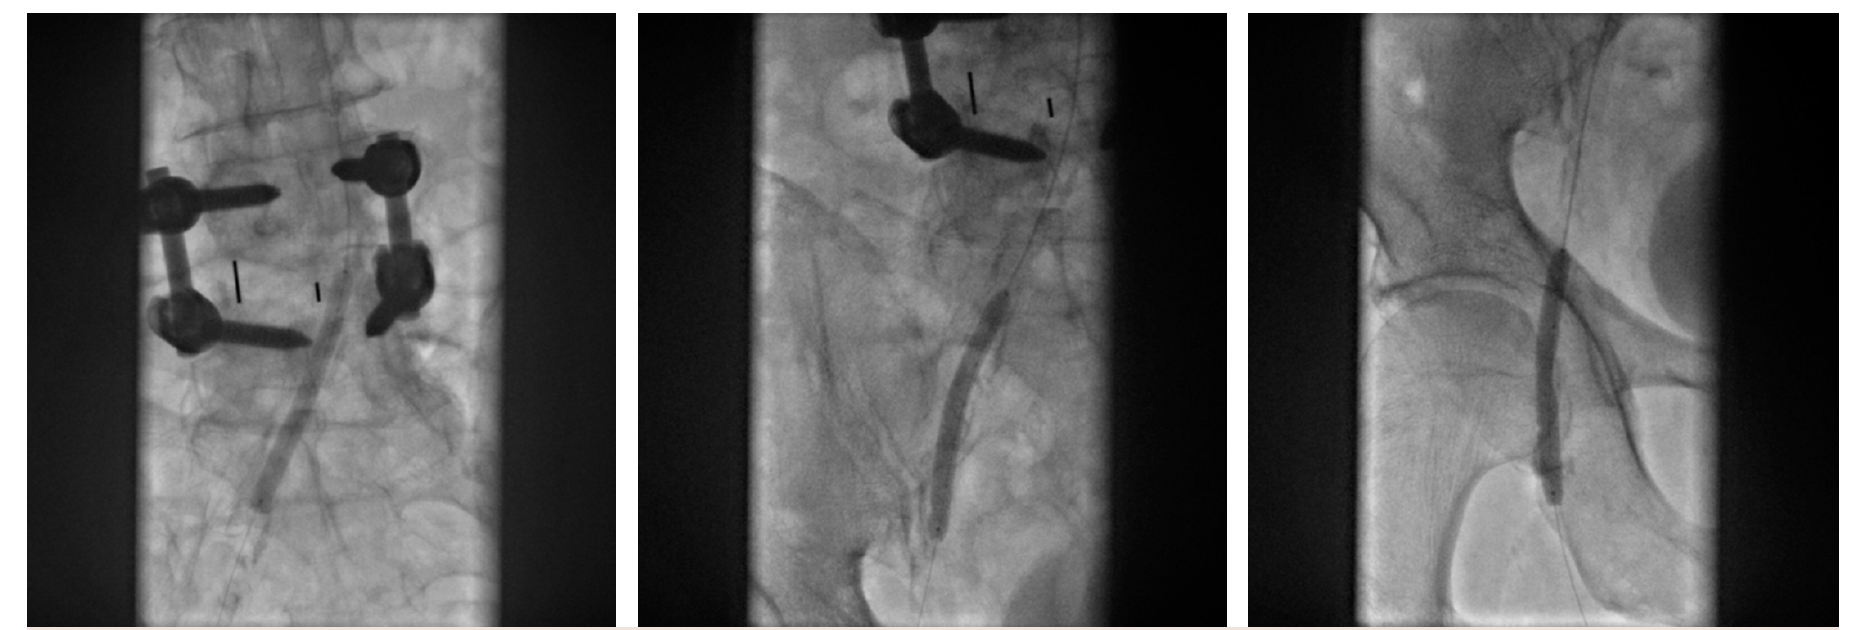

The patient was on baseline medical therapy with clopidogrel 75 mg orally daily. Anticoagulation was administered using unfractionated heparin intravenously. A 105-cm R2P Slender sheath (Terumo) was advanced into the right common iliac artery. A 0.14” wire was advanced into the distal right CFA. Over this wire, a 6-mm Shockwave M5+ IVL balloon was used to perform IVL to the right common iliac, external iliac, and common femoral arteries (Figures 2-4).